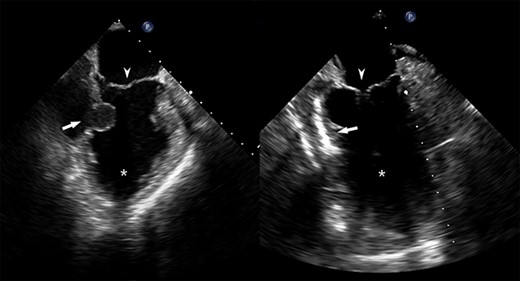

Pre- and post-repair transesophageal echocardiography images; leftward image: asterisk = left ventricular cavity, arrow = ventricular wall defect, arrowhead = mitral valve; rightward image: asterisk = left ventricular cavity, arrow = ventricular wall patch closure, arrowhead = mitral valve.

Emergent surgical intervention was performed with a median sternotomy, aorto-bicaval cannulation and antegrade cardioplegia. Dense intrapericardial adhesions were lysed, revealing a large pseudoaneurysm sac containing murky, seropurulent fluid. After debridement, a 4-cm defect in the inferolateral wall below the mitral valve was observed (Fig. 3). This was closed with an oversized bovine pericardial patch secured to healthy endocardium with a running polypropylene suture. The pseudoaneurysm edges were re-approximated over the repair in a linear fashion using two layers of suture polypropylene buttressed with felt strips. Post-repair echocardiography demonstrated no residual defect, ventricular geometry distortions or mitral valvular dysfunction (Fig. 2).